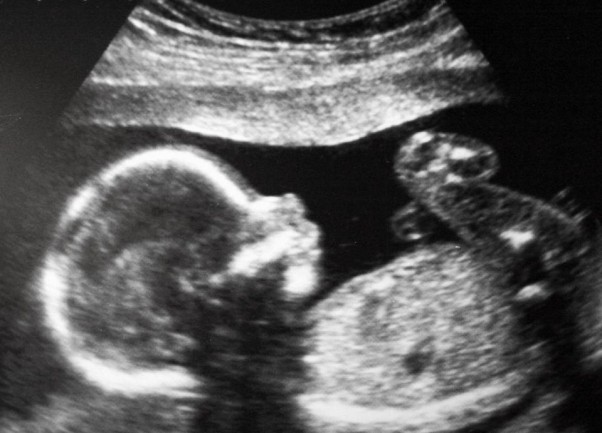

Badanie połówkowe

W końcu mamy to za sobą. Cieszę się bardzo z tego badania ponieważ pierwsze badanie prenatalne nie wyszły jakoś super ze względu na przezierność karkowa, która była w górnej granicy normy. Na szczęście dzisiaj po polowkowych już wiadomo, że wszystko jest ok więc stres był zupełnie niepotrzebny. Teraz nadszedł czas żeby już tylko się cieszyć i skompletować już wyprawkę. Dzieci już wiedzą, rodzina też już wie. Echo serca synka też już zrobione i również wszystko jest ok. Jeszcze 4 miesiące i powitam maluszka na naszym świecie.